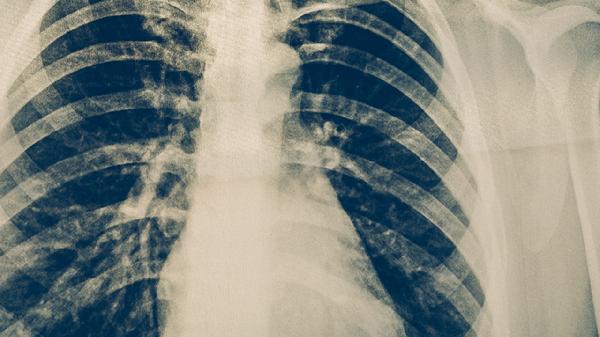

肺結(jié)核患者可以適量吃梨、香蕉、橙子、獼猴桃、草莓等水果,有助于補(bǔ)充營(yíng)養(yǎng)和促進(jìn)康復(fù)。肺結(jié)核是由結(jié)核分枝桿菌引起的慢性傳染病,患者需在醫(yī)生指導(dǎo)下規(guī)范用藥,同時(shí)注意飲食調(diào)理。

肺結(jié)核患者在選擇水果時(shí)應(yīng)注意多樣化搭配,每天攝入200-350克為宜。避免食用過(guò)于寒涼或燥熱性質(zhì)的水果,如荔枝、龍眼等。同時(shí)要保證主食、優(yōu)質(zhì)蛋白和蔬菜的均衡攝入。治療期間應(yīng)嚴(yán)格遵醫(yī)囑服藥,定期復(fù)查胸部影像學(xué)變化。保持居住環(huán)境通風(fēng)良好,適當(dāng)進(jìn)行戶(hù)外活動(dòng)增強(qiáng)體質(zhì)。如出現(xiàn)咯血、持續(xù)高熱等癥狀需立即就醫(yī)。